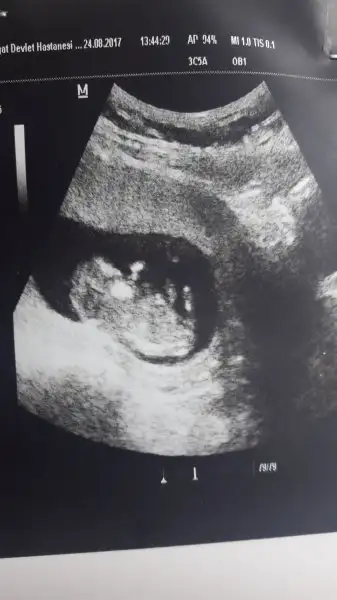

bi sıkıntı yoktur inşallah canımmDoktordan şimdi çıktık profesöre yönlendirdi

Bebeğin ensesinde sıvı birikimi varmış

Dua edin